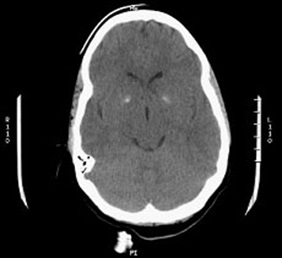

Hình 2: Chụp cắt lớp vi tính (CT) của đầu trẻ bị nhiễm HIV và viêm màng não do cryptococcus. Hiện có hai vôi hóa vân vân [6].